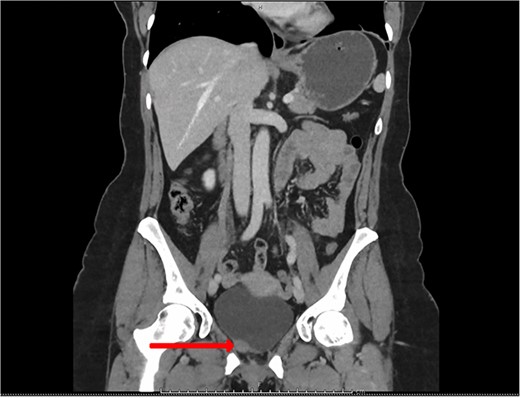

Blood tests included full blood count revealing all parameters within normal limits, eGFR >90 ml/min/1.73m2, Creatinine 64 umol/L and urea 4.5 mmol/L. Urine cultures were negative for infection. Ultrasound revealed a normal-appearing urinary tract, with both kidneys normal in size, shape and echopattern. Flexible cystoscopy revealed only a cystic lesion near the bladder dome which instigated further investigation; subsequent contrast-enhanced Computerized Tomography (CT) abdomen-pelvis scan showed a potential urachal remnant consistent with the flexible cystoscopy finding. In addition, a 1.5-cm-soft tissue structure was identified near the bladder neck which was not clearly seen initially at cystoscopy (Figs 1 and 2).

CT urogram (coronal view) revealing a 1.5 cm thickening at the level of the right lateral bladder neck and a 1-cm-soft tissue thickening at the bladder dome.